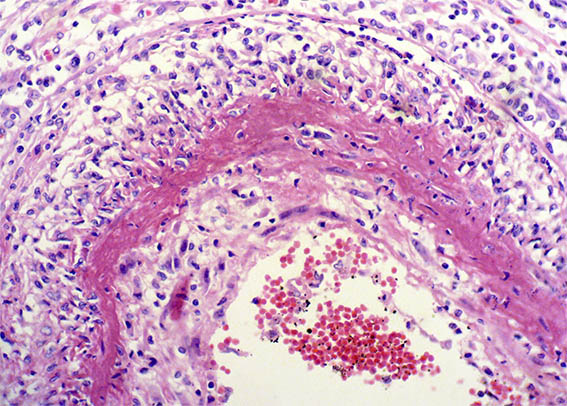

Figura 3.

H&E, X200.